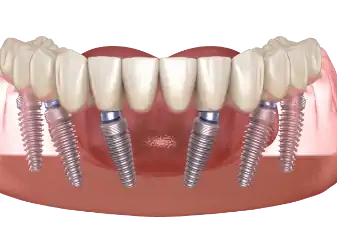

השתלת שיניים All on 4 או All on 6

השתלת שיניים All on 4 או All on 6 - המדריך עם כל המידע הרפואי והמעודכן בעבר הרחוק מי שאיבדו שיניים היו צריכים פשוט להסתדר בלעדיהן, בהמשך הופיעו שיניים מלאכותיות שעוגנו אל שיניים טבעיות שעדיין נמצאו בפה וגם מערכות של שיניים תותבות שנ